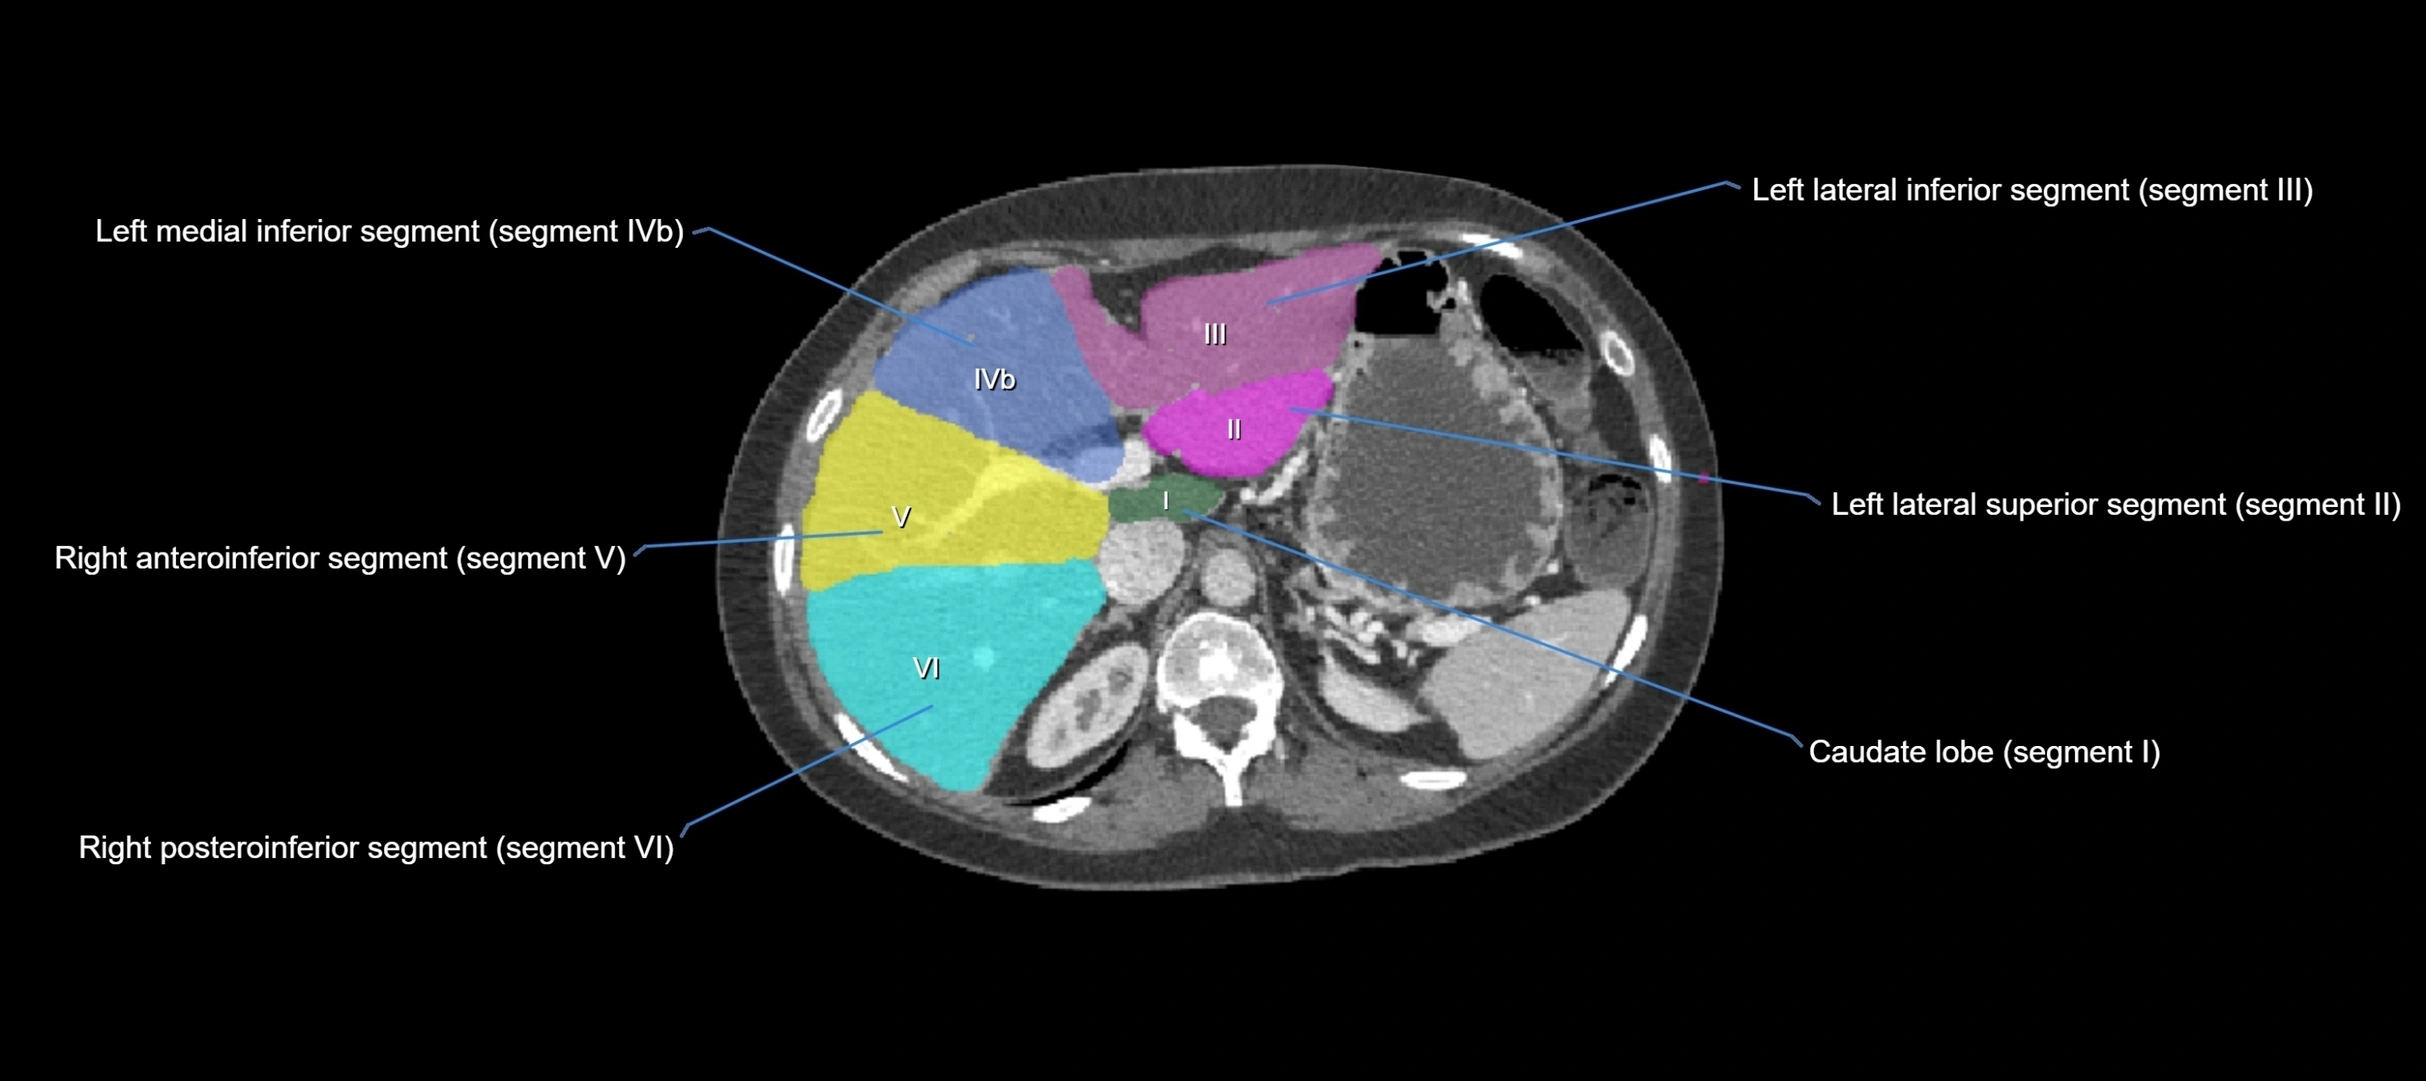

Caudate lobe of liver

The caudate lobe of the liver is a distinct anatomical subdivision of the liver, designated as segment I in Couinaud’s classification. It lies on the posterior surface of the liver, between the fissure for the ligamentum venosum (left boundary) and the groove for the inferior vena cava (IVC) (right boundary). Superiorly, it is related to the posterior liver surface, and inferiorly it is separated from the left lobe by the porta hepatis.

The caudate lobe is unique because it receives dual portal venous and arterial inflow from both the right and left portal veins and hepatic arteries. It also has independent venous drainage directly into the IVC via multiple small hepatic veins, unlike other lobes that drain through the three main hepatic veins.

This anatomical autonomy makes the caudate lobe especially significant in liver surgery, transplantation, and hepatic venous outflow obstruction syndromes (e.g., Budd–Chiari syndrome). Enlargement of the caudate lobe is a characteristic imaging feature in chronic liver disease and cirrhosis.

CT Appearance

CT Pre-Contrast:

• Caudate lobe appears as a soft-tissue density, isodense to the rest of the liver

• Enlargement may be appreciated in cirrhosis or Budd–Chiari syndrome

CT Post-Contrast:

• Homogeneous enhancement in the portal venous phase, similar to rest of liver

• Independent venous drainage into the IVC may be visualized

• Lesions follow characteristic CT enhancement patterns (HCC: arterial hyperenhancement with washout; hemangiomas: peripheral nodular enhancement with centripetal fill-in)

CT Venous Phase (functional significance):

• Caudate lobe often enhances relatively more than other lobes in Budd–Chiari syndrome, due to preserved venous outflow

CT Image

image